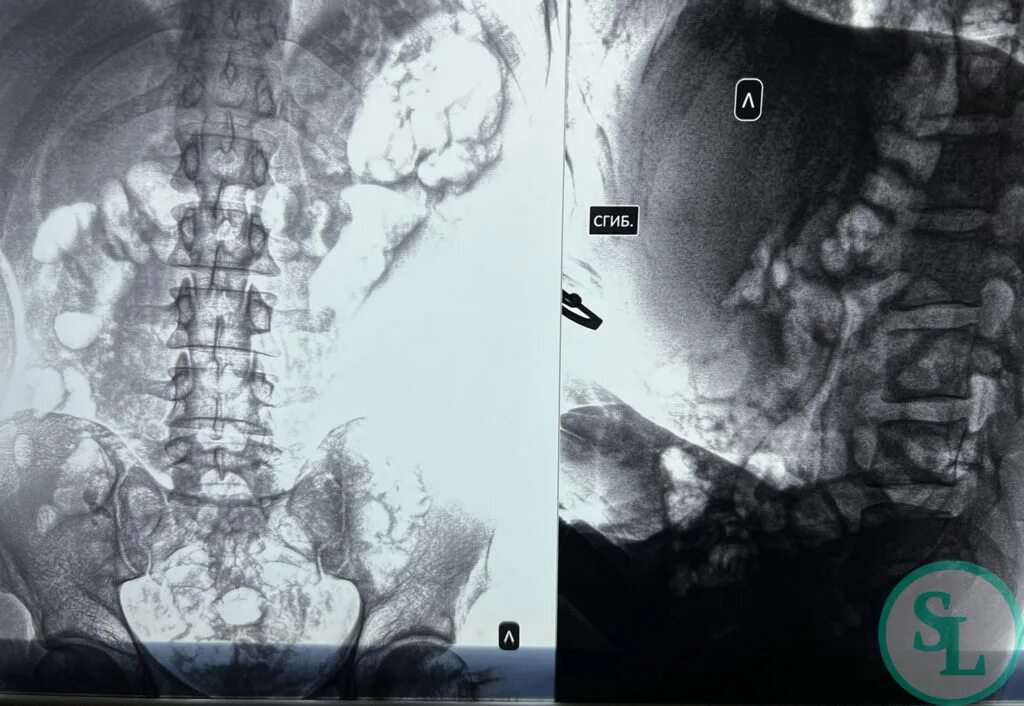

Грыжи l